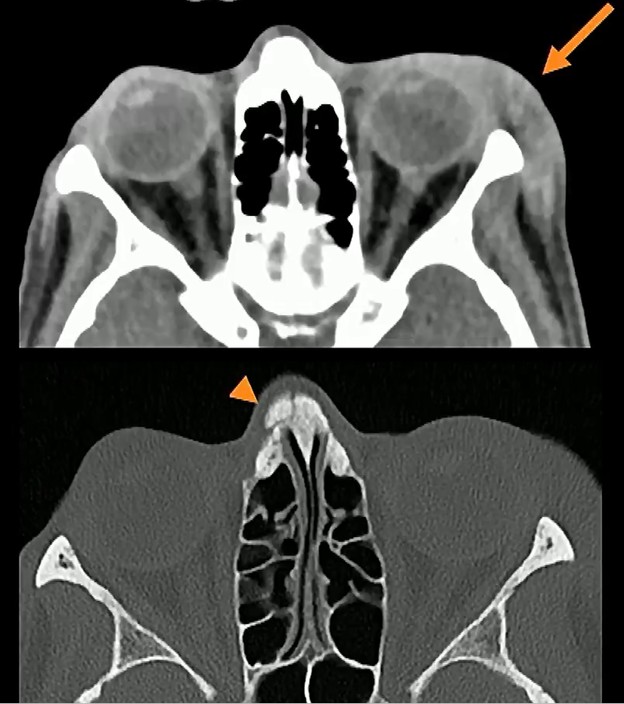

Chronic Injuries: Injuries of different ages—such as the acute periorbital hematoma alongside a chronic nasal bone fracture below—are highly suspicious for repeated cycles of abuse.

- Recurrence: Chronic fractures of the extremities and nasal bones are significantly more frequent among victims of IPV, compared to matched controls.

- Consistency: Suspicion increases when old and new injuries involve the same target or defensive side, such as the midface, hands, feet, or ankles.